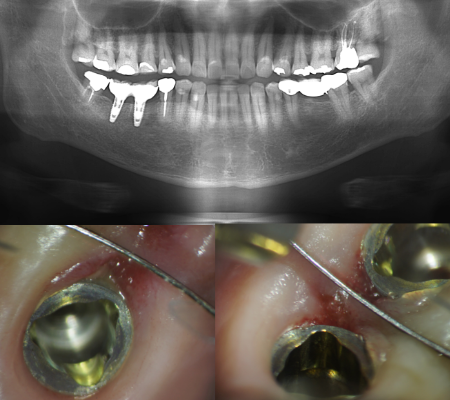

マイクロスコープとは、歯科用顕微鏡のことです。当院では最大20倍以上に拡大して患部を確認できるアメリカのGLOBAL社製のというマイクロスコープ(手術用顕微鏡)を導入しています。肉眼では難しい極細部位を安全に治療するため、精度を上げて細かく治療することができます。

レントゲンとの併用

根管は完璧な清掃を行わなければ、「痛み」「腫れ」が進み、「根尖病巣」という非常に厄介で治りにくい病気にもなります。この病変をしっかり確認するため、根幹治療を行うに際し、レントゲンで根の構造を把握しますが、CT( 三次元立体画像) も利用します。

当歯科医院のマイクロスコープは、お口の中を最大でも24倍程度、拡大してみることが出来ます。現在、歯科用顕微鏡は数社から発売されていますが、レンズの性能、操作性、精度、価格等異なりますが、当歯科医院の製品は、アメリカでは導入率が一番高いGLOBAL社のマイクロスコープ(顕微鏡)を使用しております。